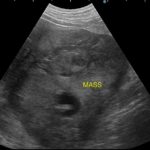

歯茎白い。すぐさま腹部の超音波検査をして”腹腔内液体貯留と腹腔内腫瘤を確認”

エコーでは脾臓と肝臓にMASSを確認。

開腹すると脾臓と肝臓に腫瘤病変があり破裂、出血していました。